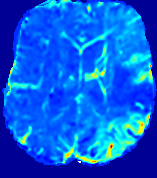

LesionRefer to captionRefer to captionRefer to captionRefer to captionRefer to captionRefer to caption𝐕rgbsubscript𝐕𝑟𝑔𝑏{\bf{V}}_{rgb}Refer to captionRefer to captionRefer to captionRefer to captionRefer to captionRefer to caption𝐕2subscriptnorm𝐕2{\|\bf{V}}\|_{2}Refer to captionRefer to captionRefer to captionRefer to captionRefer to captionRefer to captionRefer to caption3.53.53.52.82.82.82.12.12.11.41.41.40.70.70.70.00.00.0(mm/s)𝑚𝑚𝑠(mm/s)D𝐷DRefer to captionRefer to captionRefer to captionRefer to captionRefer to captionRefer to captionRefer to caption0.0200.0200.0200.0160.0160.0160.0120.0120.0120.0080.0080.0080.0040.0040.0040.0000.0000.000(mm2/s)𝑚superscript𝑚2𝑠(mm^{2}/s)Slice #1Slice #2Slice #3Slice #4Slice #5Slice #6

Figure 3: PIANO feature maps for one stroke patient, where the lesion is located in the left hemisphere. Top row: segmented stroke lesion region (white) on different slices, obtained from ISLES 2017. The corresponding slices for the PIANO feature maps are shown in the following rows.

For a better insight into an estimated velocity field 𝐕𝐕{\bf{V}} and diffusion field 𝐃𝐃{\bf{D}}, we compute the following maps: (1) 𝐕rgbsubscript𝐕𝑟𝑔𝑏{\bf{V}}_{rgb}: Color-coded orientation map of 𝐕=(Vx,Vy,Vz)T𝐕superscriptsuperscript𝑉𝑥superscript𝑉𝑦superscript𝑉𝑧𝑇{\bf{V}}=(V^{x},V^{y},V^{z})^{T}, obtained by normalizing 𝐕𝐕{\bf{V}} to unit length and mapping its 3 components to red, green, blue respectively; (2) 𝐕2subscriptnorm𝐕2\|{\bf{V}}\|_{2}: 222 norm of 𝐕𝐕{\bf{V}}; (3) D𝐷D: scalar field in Eq. 5.

Fig. 3 and Fig. 4 show the PIANO feature maps estimated from two ISLES 2017 patients: all are highly consistent with the lesion in both cases. Details of the blood flow trajectories are revealed in 𝐕rgbsubscript𝐕𝑟𝑔𝑏{\bf{V}}_{rgb} by the ridged patterns and the sharp changes of colors in the unaffected (right) hemisphere, while the flat patterns appearing within the lesion provide little directional information about the velocity and indicate low velocity magnitudes. Velocity magnitudes are more directly visualized via 𝐕2subscriptnorm𝐕2\|{\bf{V}}\|_{2}, from which one can easily locate the lesion where 𝐕2subscriptnorm𝐕2\|{\bf{V}}\|_{2} is low. D𝐷D also indicates lower diffusion values in the lesion, though with less contrast potentially due to the fact that it captures the accumulated effect of CA diffusion at the voxel-level.